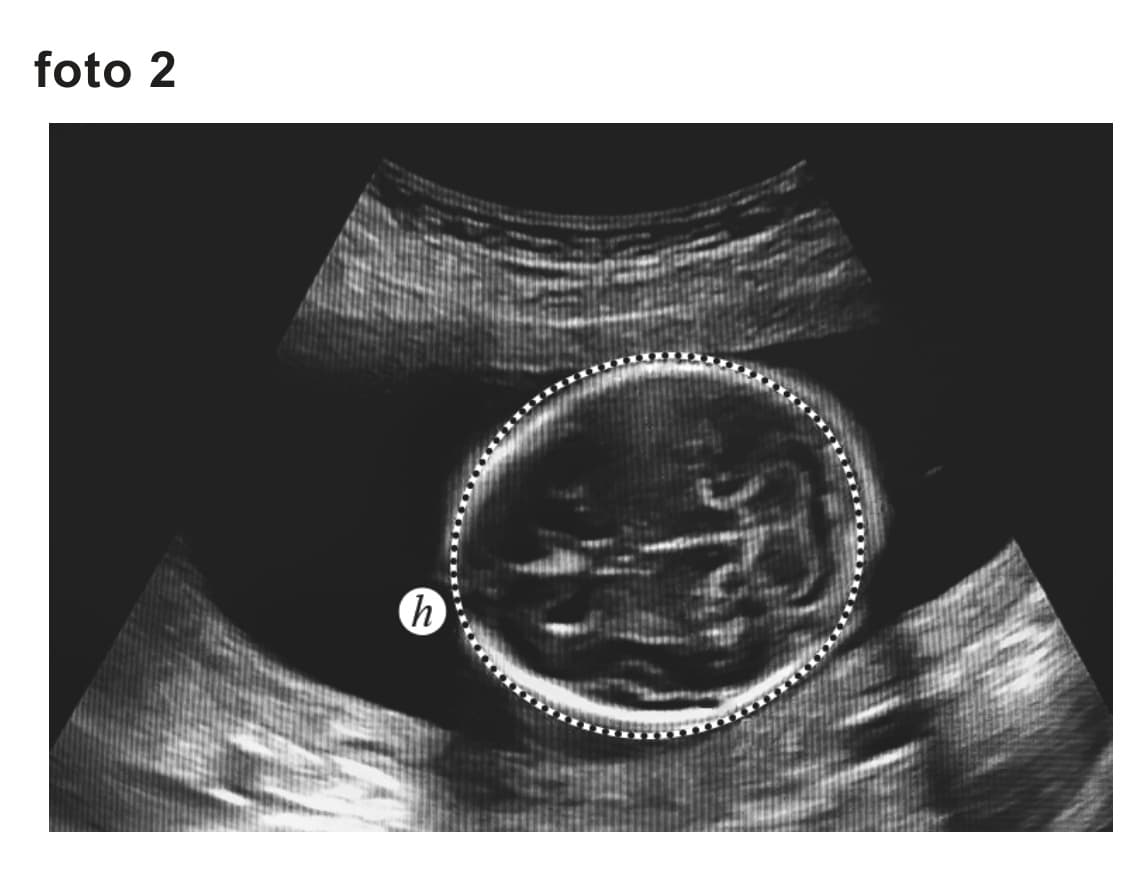

3 puntenBij een zwangerschapsduur van 8,5 tot 13 weken is de afstand bij de ongeboren baby te bepalen volgens de formule: